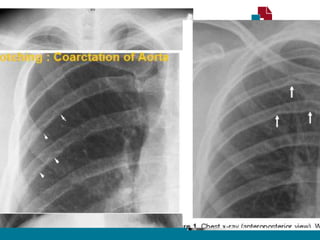

RADIOGRAFIA TORÁCICA

• Sinal de Roesler:

• Erosões bilaterais na borda inferior dos arcos costais (3ª - 9ª).

• Sinal do “ 3 invertido”

• Dilatação Subclávia E.

• Segmento estenótico aparece como um entalhe

• Dilatação pós estenótica.

• Contorno do arco aórtico apagado.